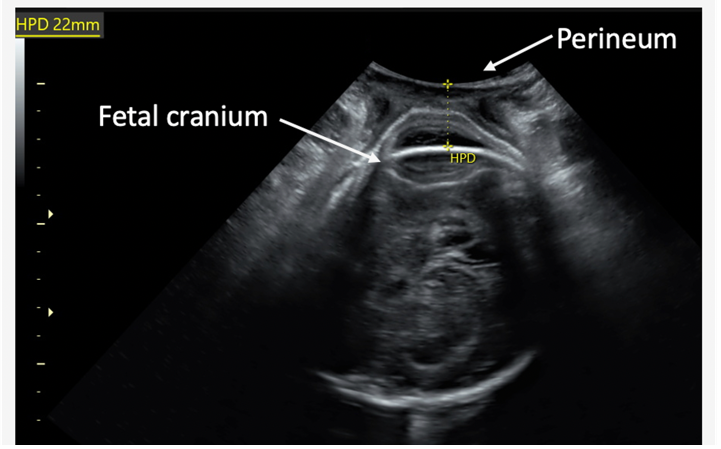

Transperineal scanning involves placing a covered and clean probe between the labia (outside the vagina) for 1-2 minutes without undue pressure, assessing the baby's descent in the birth canal. Both the transabdominal and transperineal scans are performed as part of this study. The total scan time is 5 minutes and routine care in labour is not affected. Information from the ultrasound scans may help us to predict whether a caesarean section or assisted vaginal birth will be needed and thus may help guide women and birth attendants in the future.